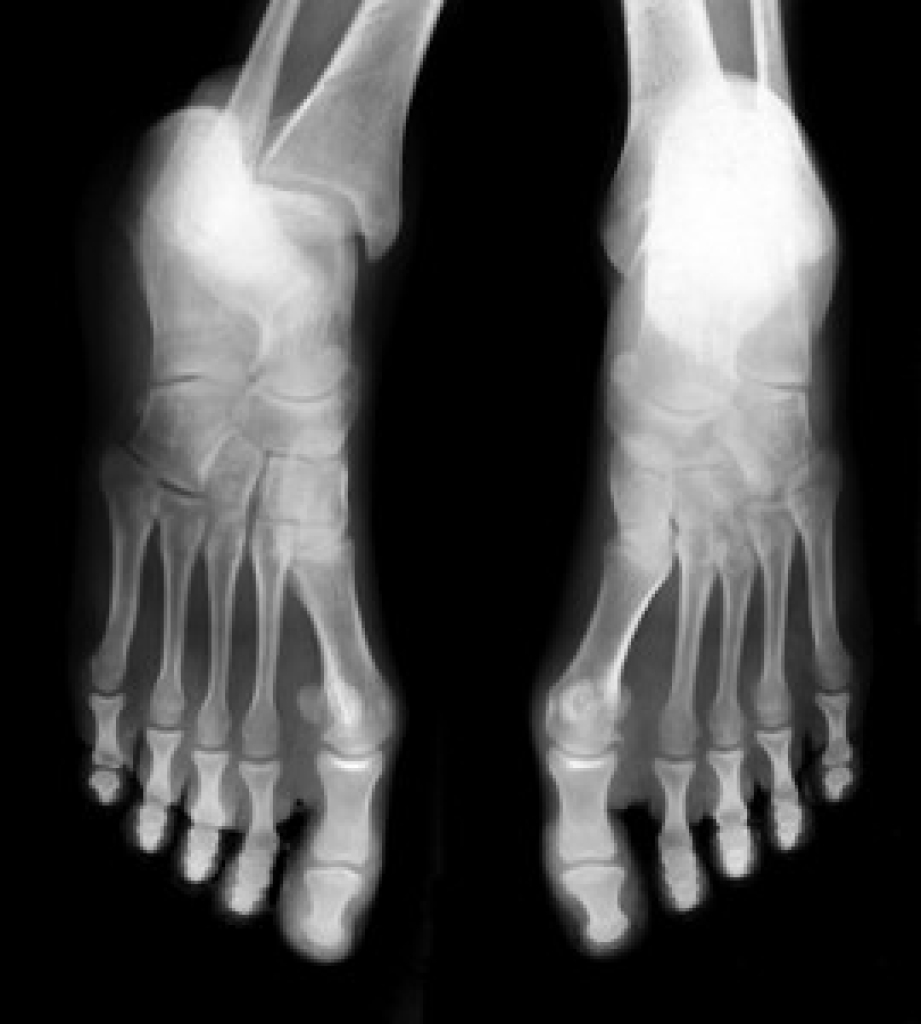

Heel pain is often associated with plantar fasciitis. The plantar fascia is a band of tissues that extends along the bottom of the foot. A rip or tear in this ligament can cause inflammation of the tissue.

Heel spurs are another cause of pain. When the tissues of the plantar fascia undergo a great deal of stress, it can lead to ligament separation from the heel bone, causing heel spurs.